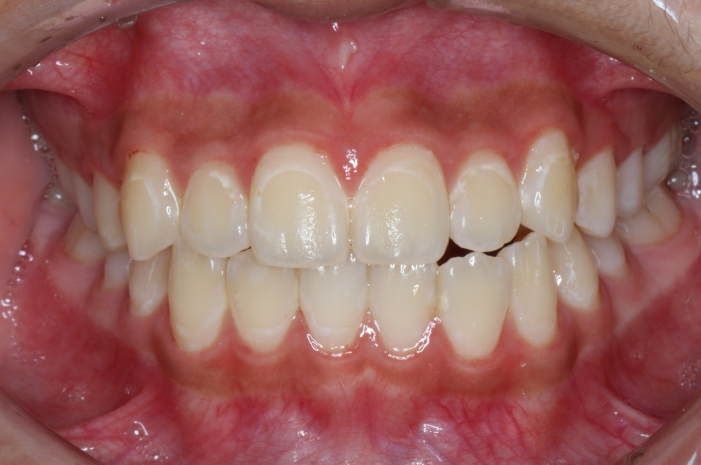

| 患者様データ | 20代 女性 |

| 来院時の主訴 | 「歯茎から自然に出血する。」 |

| 医院の診断 | 歯肉炎 |

| 通院期間 |

1か月 |

| 来院回数 | 4回 |

| 治療費 | 総額:保険適用診療 【内訳】 歯周病検査・歯磨きや生活習慣指導・歯石取りクリーニング |

| リスクと副作用 | メインテナンスが必要、正しい歯磨き習慣が必要不可欠 |

| ここがこだわりのポイント!☝ | 歯周病の原因は様々ですが、メインの原因は細菌感染です。こちらは歯周病初期の歯肉炎の状態で来院された患者様です。日々の歯磨き習慣を見直していただき、正しいブラッシング法を身につけたことで健康な歯肉を取り戻しました!治療結果は患者様の努力の賜物です! |